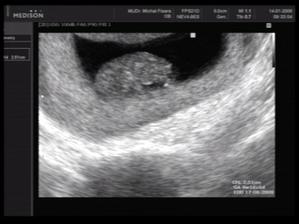

Vytoužené zlatíčko

Ahoj holky, toto je moje - teda naše vytoužené miminko po 9ti letech boje. Celé těhu si opravdu užívám...až na tu únavu, ale moje mimi si může ze mě vzít cokoliv.